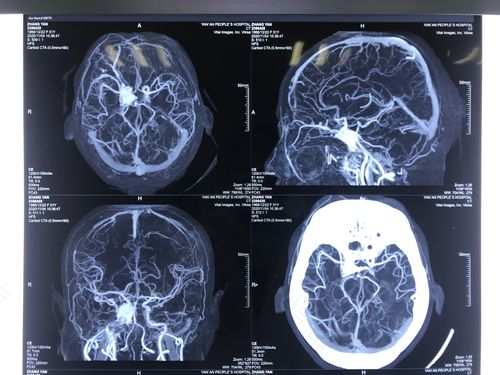

因血肿的形态及部位的不同而有不同的手术治疗方法。

(一)开颅减压手术

因严重头部外伤,或因桥静脉破损形成巨大血块时,需以开颅减压手术来摘除血块。而新生儿因产伤所造成的上颅窝、或后颅窝硬脑膜下血肿及颅内高压时,以及颞窝蛛网膜囊并发的硬脑膜下血肿也需以此手术除去血块。